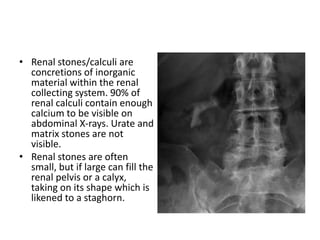

• Renal stones/calculiare concretions of inorganic material within the renal collecting system. 90% of renal calculi contain enough calcium to be visible on abdominal X-rays. Urate and matrix stones are not visible. • Renal stones are often small, but if large can fill the renal pelvis or a calyx, taking on its shape which is likened to a staghorn.

• Renal stones/calculi are

concretions of inorganic

material within the renal

collecting system. 90% of

renal calculi contain enough

calcium to be visible on

abdominal X-rays. Urate and

matrix stones are not

visible.

• Renal stones are often

small, but if large can fill the

renal pelvis or a calyx,

taking on its shape which is

likened to a staghorn.